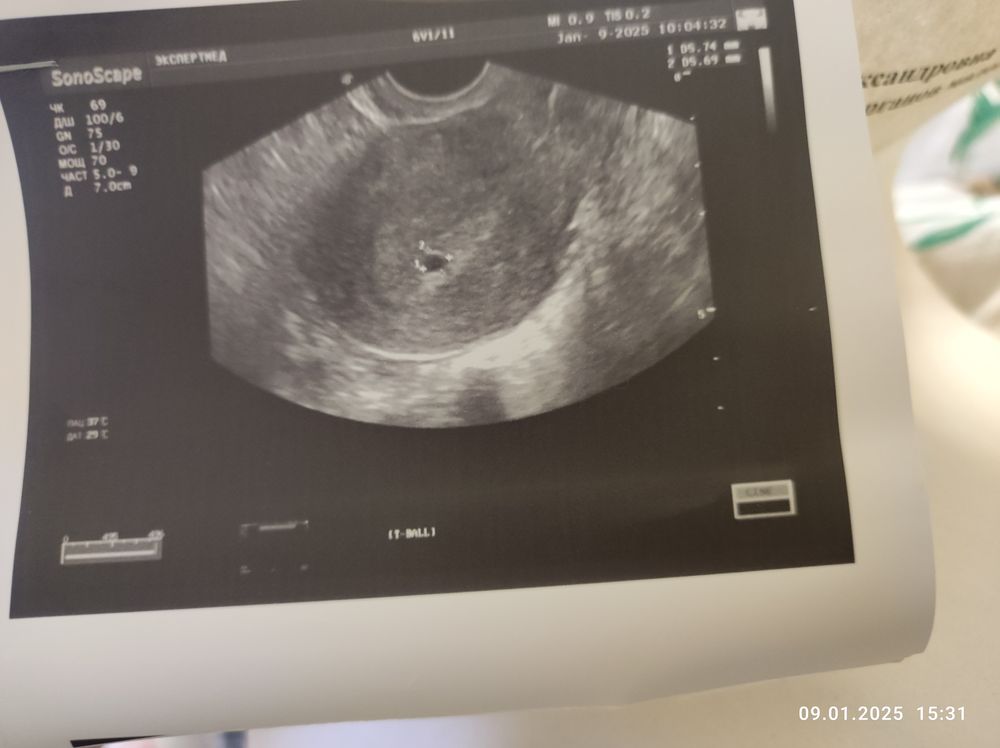

4 эмбриональные недели узи

4 эмбриональные недели узи 148 фотографий